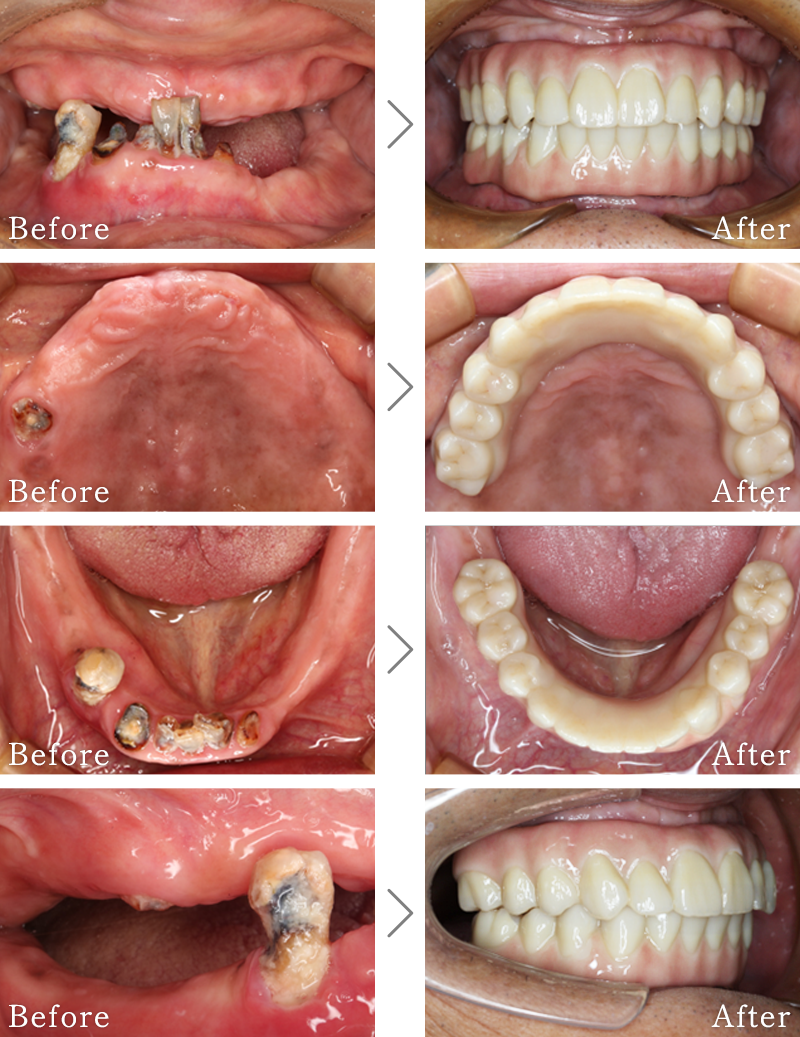

CASE1

主訴 入れ歯も合わず、しっかりと噛んで食事ができないとのことで来院されました。

治療法 上下ともにALL-ON-6と呼ばれる最少本数のインプラントで全ての歯を回復する治療を行なっています。歯の部分は全てセラミックで作成されています。

治療期間 5ヶ月

費用 CT:16,500円(税込)

+ 静脈内鎮静法:66,000円(税込)

+ ALL-ON-6×2:5,500,000円(税込)

合計:5,582,500円(税込)

CASE6

主訴 入れ歯が合わず、痛くて噛めない。食事ができない。

治療法 入れ歯を新しく作成し、噛み合わせなどの確認をしたのち、左右2本ずつインプラントを使用して噛める状態に回復させています。

+ インプラント治療:2,321,000円(税込)

合計:2,403,500円(税込)